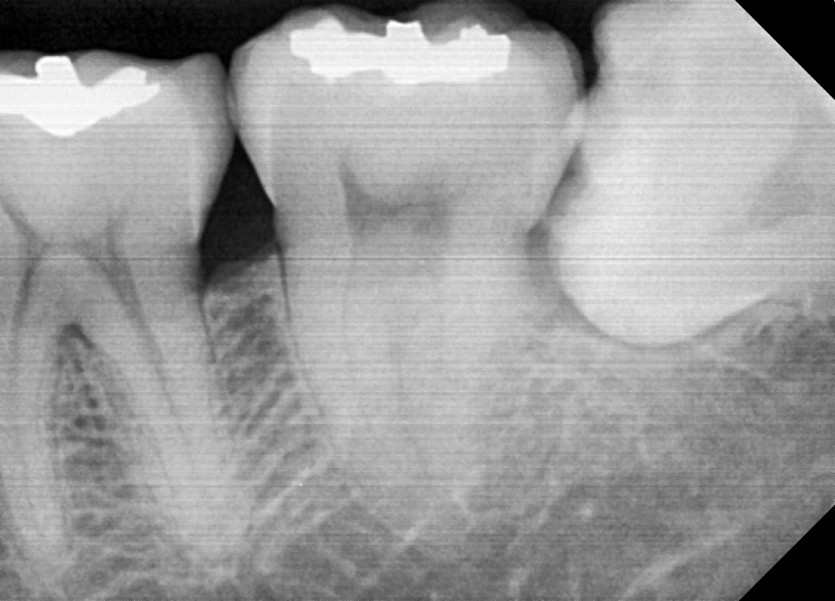

#38 사랑니 발치

구강외과 전문의가 당일 발치하였습니다.